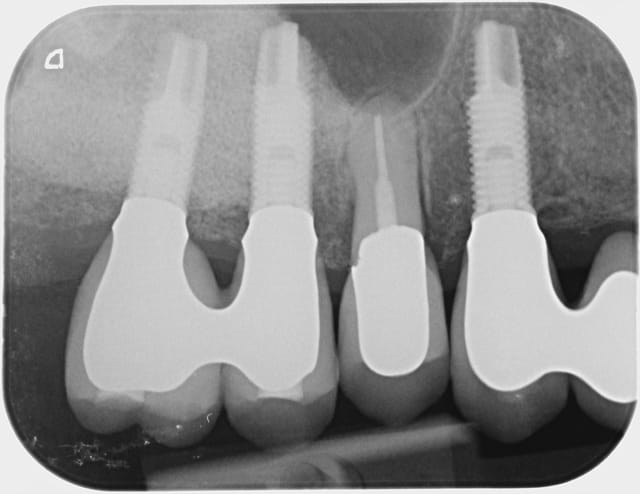

Bon alors revenons a cette 15.

On voit bien sur l'historique radio que la migration apicale a débuté entre janvier et mai 2014. Date à laquelle j'ai dû changer la 14.

J'aime bien les points de contacts assez serrés et là j'ai le souvenir qu'il était très costaud.

Je pense donc que la migration est dû a une compression de la 15 par effet de coin comme la supputer Shadow.

De toute manière maintenant elle ne bougera plus!

A 10 mars 2008 hjqdhq - Eugenol

B 22 mai 2009 fhhmrm - Eugenol

C 04 juin 2009 vjcx5r - Eugenol

D 15 juin 2009 od7vwg - Eugenol

E 25 juin 2009 hht4ji - Eugenol

F 18 novembre 2009 hhywkg - Eugenol

G 21 janvier 2011 xurlrw - Eugenol

H 19 fevrier 2013 tvy4db - Eugenol

I  21 janvier 2014 gyys5o - Eugenol

J 21 mai 2014 i8zdgv - Eugenol

Jj 16 octobre 2014 clat7g - Eugenol

Jjj 16 otobre 2014 yevkyg - Eugenol

K  6 novembre 2014 lfkxbg - Eugenol

L  6 novembre 2014 gcsqeq - Eugenol

M  6 novembre 2014 gc5q3z - Eugenol

P  6 novembre 2014 cy54gy - Eugenol

Q  6 novembre 2014 vtispk - Eugenol

R  6 novembre 2014 nrhlqf - Eugenol